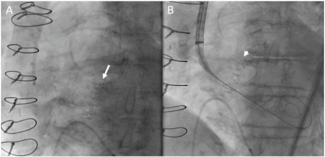

Antonios Ziakas, MD; Konstantinos C. Theodoropoulos, MD, MSc; Antonios Kouparanis, MD; George Kassimis, MD, PhD

Clinical images demonstrating stent damage during the insertion in the distal cylinder of the Telescope GCE.